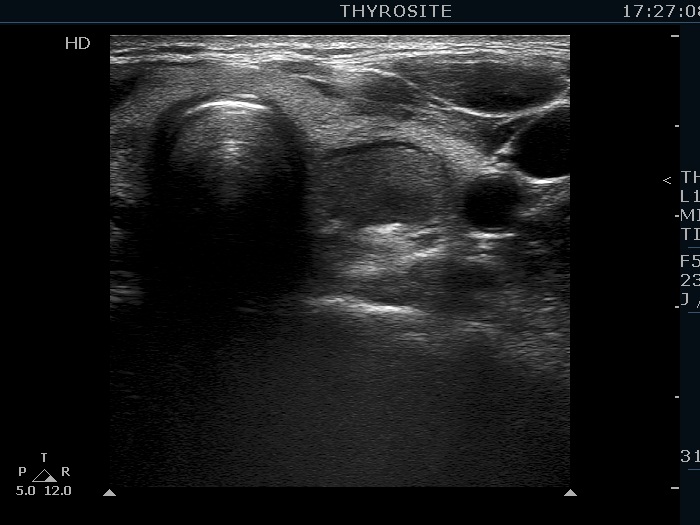

Ultrasonography. The thyroid was echonormal. There were several hypoechogenic lesions in the right lobe. The left lobe had an upper, solid and a lower cystic nodule. The former had both echonormal and moderately hypoechogenic parts and presented halo sign. The cystic nodule had a very tiny solid area in the dorsal part. Nonetheless, before aspiration it was unclear whether this would be a pure cyst or not. After aspirating 2 mL serous fluid a large, moderately hypoechogenic solid area replaced the previous cystic field and it became evident that this is in fact a central type cystic nodule.